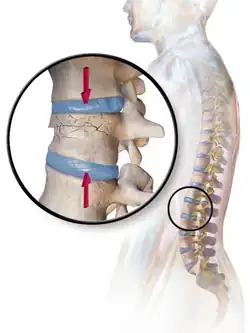

| Example of vertebral compression fracture. | |

A compression fracture is a collapse of a vertebra. It may be due to trauma or due to a weakening of the vertebra (compare with burst fracture). This weakening is seen in patients with osteoporosis or osteogenesis imperfecta, lytic lesions from metastatic or primary tumors,[1] or infection.[2] In healthy patients, it is most often seen in individuals suffering extreme vertical shocks, such as ejecting from an ejection seat. Seen in lateral views in plain x-ray films, compression fractures of the spine characteristically appear as wedge deformities, with greater loss of height anteriorly than posteriorly and intact pedicles in the anteroposterior view.[3]